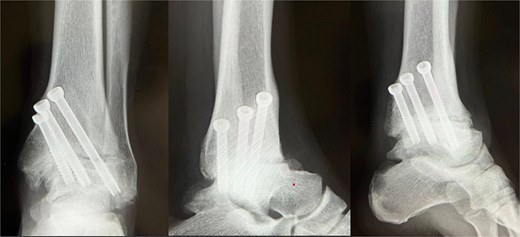

Preoperative radiographs and computed tomography (CT) demonstrated complete loss of the tibiotalar joint space, talar subluxation, and extensive osteophyte formation consistent with end-stage post-traumatic osteoarthritis (Figs 1 and 2). After informed consent and institutional review board approval (IRB number #20251001), the patient underwent arthroscopic ankle arthrodesis.

Preoperative radiological imaging: X-ray finding. The patient presented with end-stage osteoarthritis of the tibiotalar joint, characterized by flattening of the joint surface and subluxation of the talus (↓). Although mild arthritic changes were observed in the subtalar joint (⇓), its articular surface remained preserved.